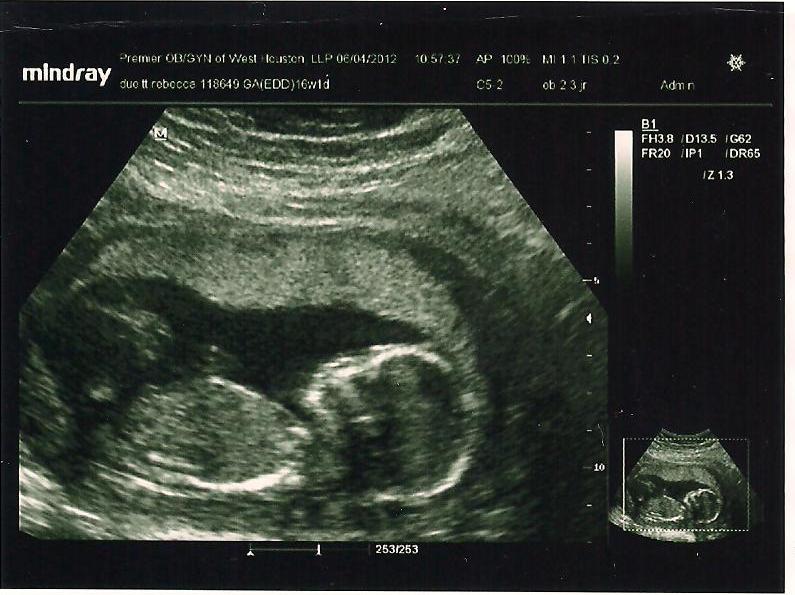

| 20 Weeks and 16 Weeks |

After literally traveling and being away from home for 3 weeks, I was due for my 4th doctors appt. This was supposed to be my 20 week appt where they go over all of the organs, body systems, check gender again, and make sure everything is forming correctly. Since I had been traveling, this was technically 22 weeks for me. The appt was on July 16th. Everything was perfect! It was an *extra* special appt again because not only did Drew come but my Mom was able to come and see Charlotte moving on the screen. We were so thrilled to see our baby girl for the 4th time and hear her beautiful little heart beating.

| 22 Weeks, our little Charlotte |